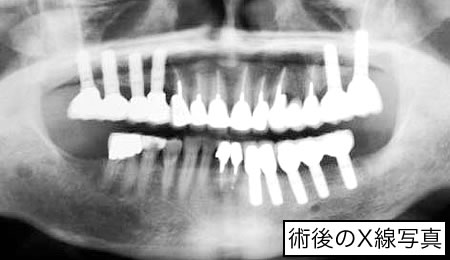

最近のインプラント治療は、以前のように、噛めることを優先とした治療だけでなく、見た目(審美性)まで考慮した治療へと移行してきています。また、以前までは、骨がない部分にはインプラント治療はあきらめざるを得なかったところに、骨を再生させ、骨量を増大させることによりインプラントを植立することが可能になってきています。しかし、このような治療には術者の高度な技術が要求されるのも確かです。

また、インプラント治療を受けられる患者さんでは、その他の歯牙や歯周組織においても問題を抱えている場合が多く、一口腔単位での治療が必要になる場合がほとんどであるといえます。噛み合わせや歯の根っこの治療(根間治療)、歯周治療、虫歯の治療をおろそかにしてインプラント治療の成功は望めないといっても過言ではないでしょう。 |